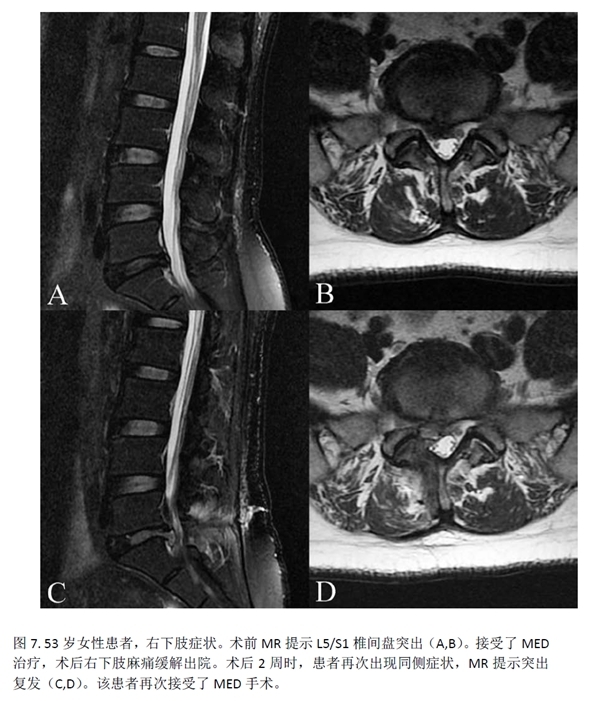

此外,2例(2.5%)PTED组患者及7例(9.59%)MED组患者出现新发患肢麻木感,但两组间没有统计学差异。MED组还有1例(1.36%)患者发生伤口愈合不良。PTED组有5例(6.25%)患者因复发/残留而需进行再次手术,MED组则为3例(4.11%)。再次手术率方面,两组之间没有统计学差异(p=0.818)。